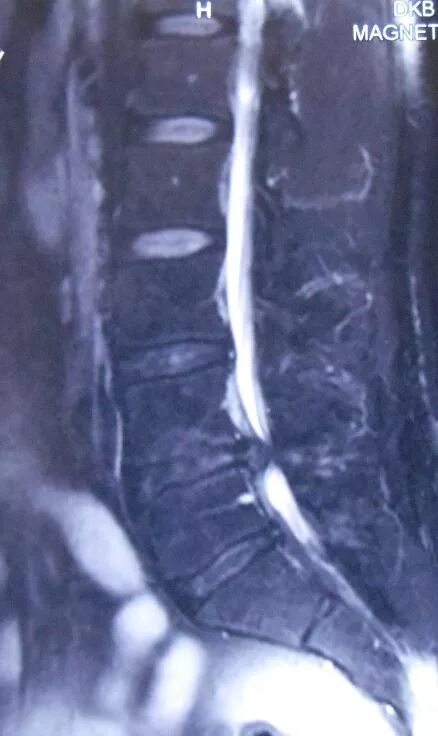

Операция грыжа l5 s1